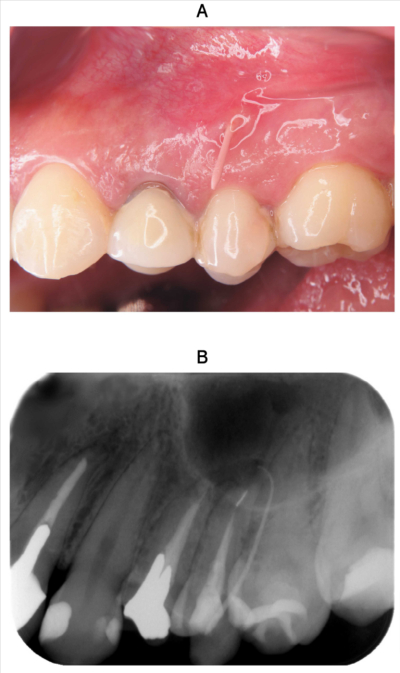

28歳の女性。上顎左側第二小臼歯の歯肉腫脹を主訴として来院した。5年前に治療を受けたが、3か月前から歯肉が腫れてきたという。垂直打診で鈍痛がみられる。慢性化膿性根尖性歯周炎と診断した。瘻孔からガッタパーチャポイントを挿入した口腔内写真とエックス線写真を示す。

原因として考えられるのはどれか。1つ選べ。

a. 器具破折

b. 歯根破折

c. 根尖部穿孔

d. レッジ形成

e. 根管充塡材溢出